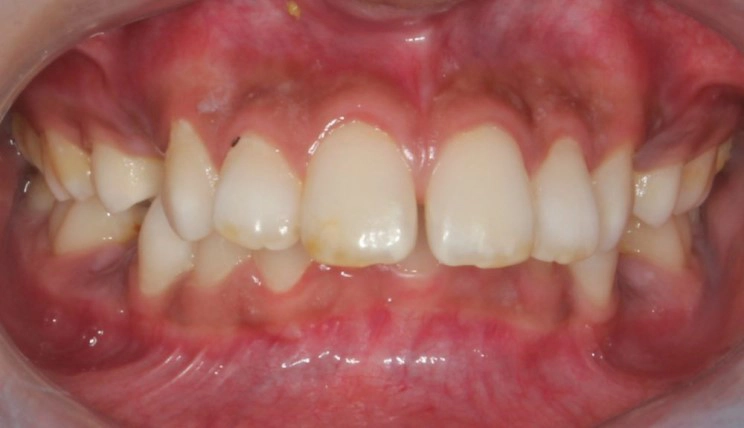

Posterior Crossbite

Posterior crossbite is the abnormal labiolingual relationship between one or more upper and lower posterior teeth, resulting in the upper teeth being positioned lingual to the lower teeth, or the upper teeth being positioned so buccal to the lower teeth their lingual face slides against the lowers buccal face.

Patient Information:

Age: 24

Gender: Female

Invisalign Treatment Option: Invisalign Comprehensive

Total Treatment Time:

29 months